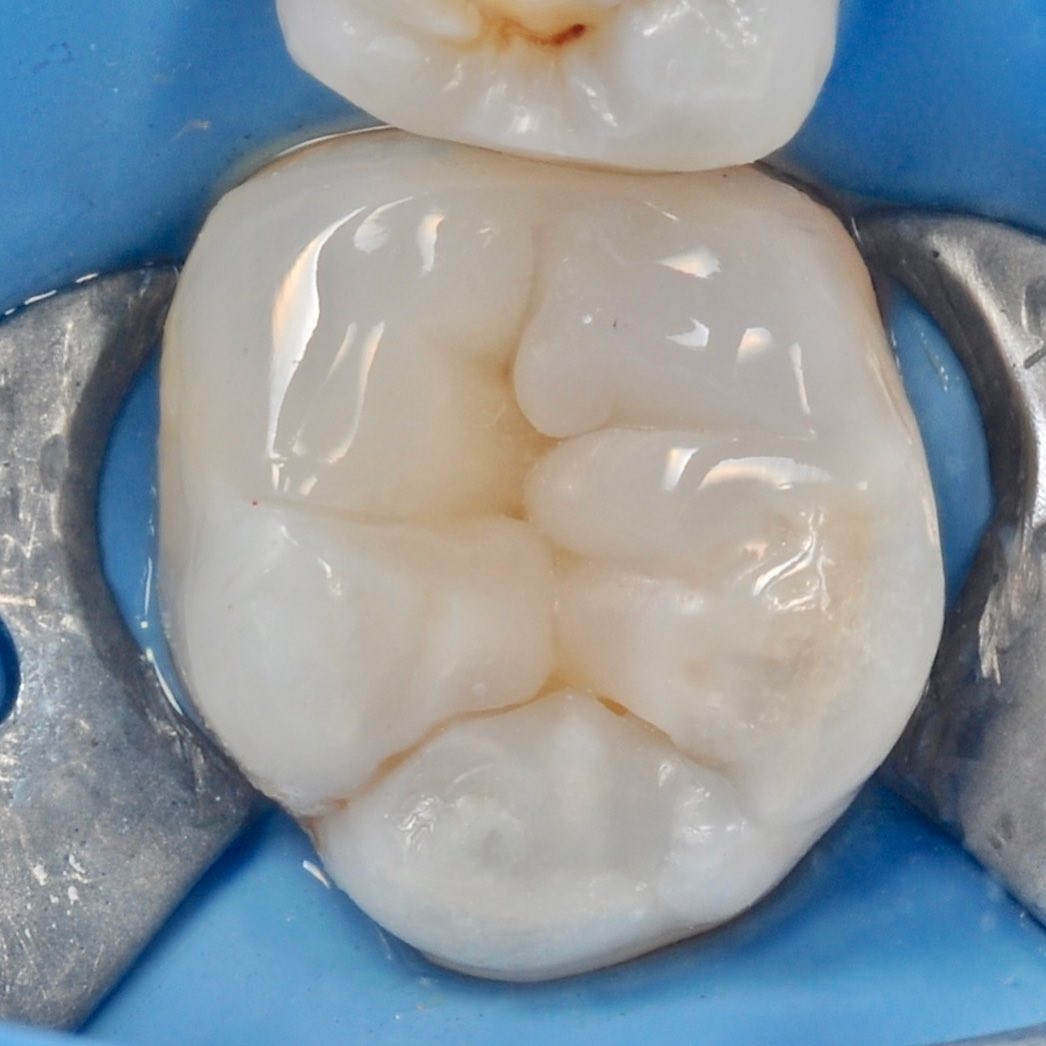

careful treatment of canals

Accurate determination of the geometry of the channels and their high-quality processing

polishing